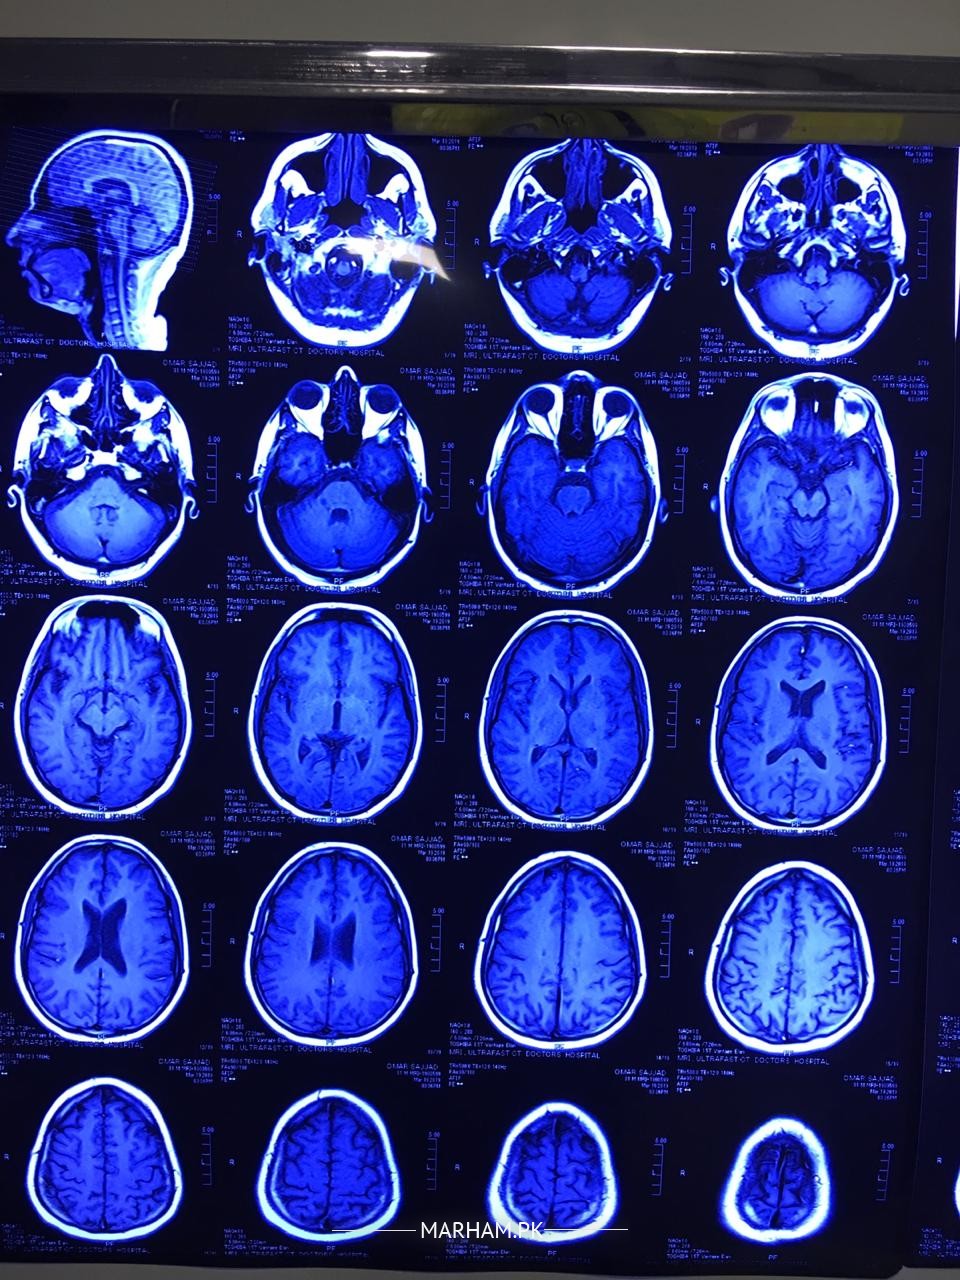

my husband had numbness in his right side of face half head. we consulted a doctor he recommended some tests and MRI. i m attaching some images plz help us understand what is the issue. m attaching all reports and images.

He is a young man and the MRI reports reveal a disease called as Multiple Sclerosis. It a disease in which body's own immune or defence system starts working against own brain tissues. It requires thorough investigations including Lumbar puncture, taking sample of fluid of brain from the spine , and few more tests. It is a chronic disease and you need to consult a neurologist so that appropriate plan of treatment can be discussed in detail.

The MRI scan report seems to suggest a diseases called Multiple Sclerosis. the dis have a deep blue tinge, therefore cannot be reliably commented upon. First the diagnosis needs to be confirmed, with contrast MRI scan and some other tests. then if it's really multiple Sclerosis then a Neurologist will discuss treatment options with you. there are good options available now to control the disease. however, I repeat , most importantly the diagnosis must be confirmed. for that you need to see a neurologist. neurological history and examination are as important as lab tests to diagnose this condition. please show a Neurologist in your city

mri brain finding are suggestive of most likely multiple sclerosis. a disease of demyelinating in nature . need detail history about your husband .